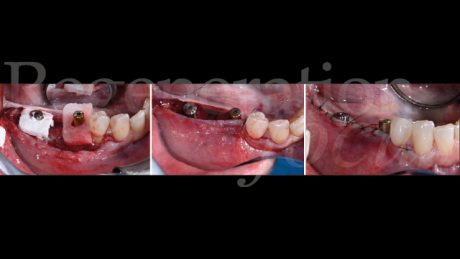

L’intervento chirurgico è stato eseguito in anestesia loco-regionale. È stato elevato un lembo trapezoidale composto da un’incisione crestale e da un’incisione verticale di svincolo posizionata due elementi mesialmente al difetto, mentre distalmente l’incisione è proseguita nella regione retromolare (Fig. 4). Particolare attenzione è stata posta al rilascio periostale, eseguito sia vestibolarmente che lingualmente, permettendo una mobilizzazione coronale di entrambi i lembi di circa 8 mm senza tensione.

La mesh customizzata si è adattata perfettamente al sito ricevente, confermando la precisione della pianificazione digitale (Fig. 5). Il materiale da innesto è stato preparato combinando osso autologo particolato, raccolto dalla linea obliqua esterna mediante grattino monouso (SafeScraper, Meta), con osso bovino deproteinizzato di granulometria 0,25-1 mm (Geistlich Bio-Oss®) in rapporto 50:50. A questa miscela sono stati aggiunti 0.3 ml di gel a base di polinucleotidi e acido ialuronico (Regenfast®), creando una mixture bioregenerativa che è stata accuratamente compattata all’interno della mesh (Fig. 6).

La fissazione è stata ottenuta mediante tre viti in titanio da 1.5×5 mm (Viti FYxoss, MCbio) posizionate strategicamente (Fig. 7). Una membrana in collagene 30×40 mm (Geistlich Bio-Gide®) è stata posizionata a copertura della mesh (Fig. 8). La chiusura primaria tension-free è stata ottenuta con suture orizzontali a materassaio e punti staccati (Fig. 9).

Il follow-up a 2 e 4 settimane ha documentato la guarigione per prima intenzione. A 6 mesi, la CBCT ha evidenziato eccellente integrazione dell’innesto con ottimale densità ossea (Fig. 10). La seconda fase chirurgica ha previsto la rimozione della mesh e l’inserimento simultaneo di due impianti tissue level (3.7 x 10 mm plat. 3.7 in sede 45; 3.7 x 8 mm plat. 4.5 in sede 47) caratterizzati da un design transmucoso concavo di 1.8 mm con superficie anodizzata (Matrix Line, TRI Dental Implants) (Fig. 11). Il torque di inserimento di 45 Ncm ha confermato l’ottima qualità ossea.